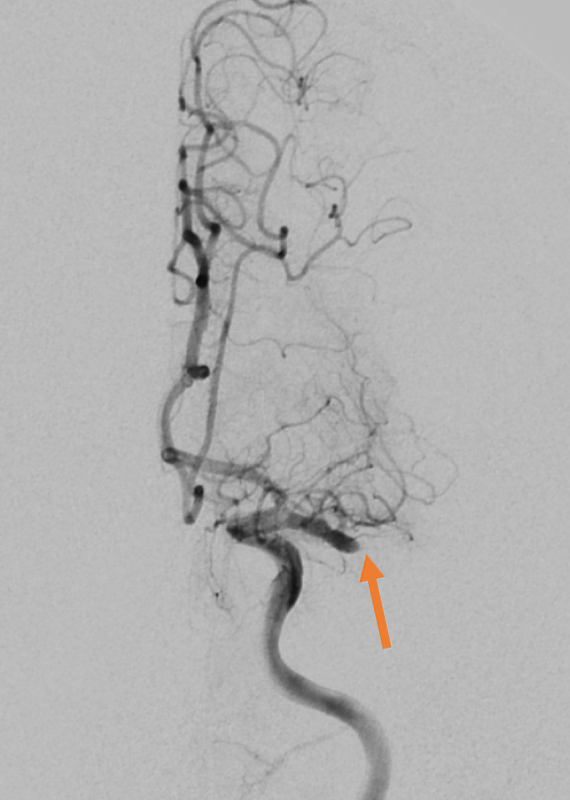

以取栓治療而言,從鼠蹊部置入導管,穿過股動脈到中大腦,醫師透過導管輕巧將抽吸或支架取栓裝置放到阻塞位置進行血栓移除,順利移除血栓後,受影響中風區域組織與細胞有可能大程度保留並得到較佳的復健效果。花蓮慈院目前執行取栓治療的醫師有影像醫學部高鴻文主任、神經影像科主任薛俊仁、神經介入診療科主任阮郁修、神經外科李建輝醫師部等醫師。

高鴻文主任舉例,一位五十二歲男性有高血壓病史病人,發病後滿分五分的力氣僅剩二分,在中大腦動脈血栓堵住情況下,經過取栓後讓血流順利通過,將大腦損傷降到最低。另一位病人是七十五歲伯伯,也是左邊中大腦動脈血栓堵住,到院時右側肢體僅剩二分力氣,口齒不清,病史包括糖尿病、高血壓、心臟病,經過取栓微創手術治療打通動脈後,讓大腦及時得到救援。